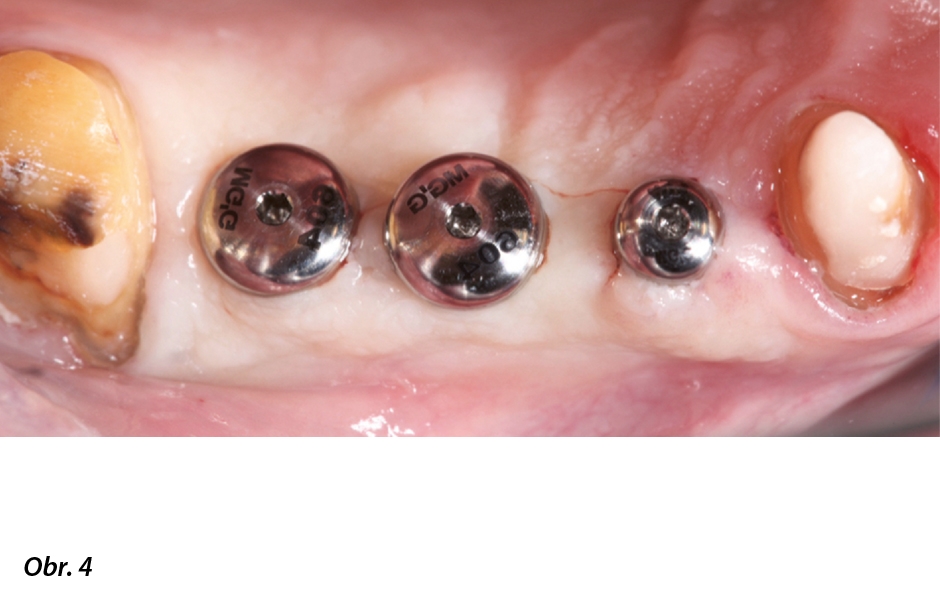

Ve většině případů je nutná rozsáhlá rehabilitace a rekonstrukce v horní i dolní čelisti. Často jsou navíc nutné velké augmentační zákroky, které značně prodlužují dobu ošetření i hojení (obr. 2a–i, 3a–g). Před zahájením ošetření zahrnujícího fixní náhradu je proto nutné zajistit, aby pacient zvládal udržovat vysoký a trvalý standard ústní hygieny. S ohledem na stárnutí populace je při určování prognózy a životnosti definitivní náhrady nesené implantáty zásadní schopnost spolupráce ze strany pacienta. Cílem náhrady nesené implantáty totiž musí mj. být dosažení stavu měkkých tkání v okolí implantátů, který bude klinicky stabilní a proteticky adekvátní (obr. 4, 5).

Obr. 4, 5: Stabilní, zdravé a dobře vytvarované měkké tkáně v okolí implantátu jsou základním předpokladem a prvkem ošetření nezbytným pro udržitelnou suprastrukturu kotvenou na implantátech.